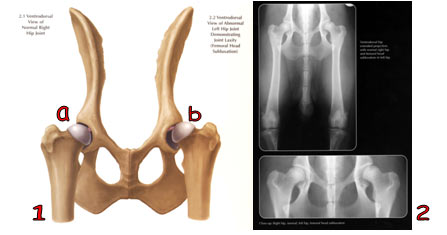

1a. Gambaran ventrodorsal persendian pinggul normal.

1b. Gambaran ventrodorsal persendian pinggul yang menderita luksasi caput femoralis.

2. Gambaran radiologi ventrodorsal gambar 1.